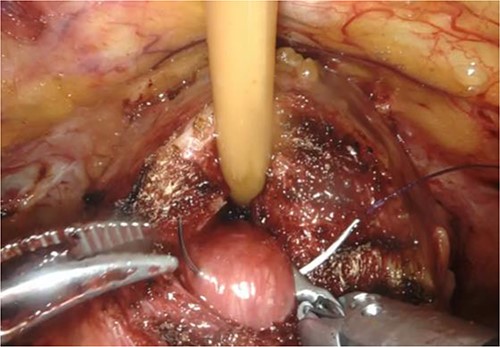

RARP was performed without preoperative hormone therapy. All steps of the RARP procedure were based on a previously established method described by Patel et al. [5], in which all procedures were performed via the transperitoneal approach with a six-port technique. In our patient, we performed conventional RARP. In cases with middle-lobe hypertrophy, prostate dissection around the bladder neck is an important feature. In this procedure, the border between the bladder neck and prostate is dissected using electrocoagulation, and when the middle lobe of the prostate is exposed, it is punctured using a 25-cm, 26-mm, 3–0 monofilament needle and lifted using the fourth arm several times (Fig. 2). The manual procedure, involving pulling in various directions and re-puncturing when the middle lobe is exposed, is repeated until the middle lobe is completely exposed. This reveals the bladder trigone and ureteral orifice and allows identification of the appropriate resection line. At this point of the dissection, the prostate is dissected, the dorsal seminal vesicle is penetrated, and finally, the Denonvilliers fascia is dissected (Fig. 3). Surgery was completed without additional suturing in the bladder neck side. The console time was 2 h 9 min, and the anesthesia time was 3 h 40 min. Bleeding volume was 28.5 ml, including urine volume. The weight of the removed prostate was 70 g. The pathological features were as follows: tumor size 10 × 5 mm (largest tumor layer); Gleason score 4 + 3 = 7; and adenocarcinoma pT2c, ly0, v0, pn0, sv0, EPE0, and RM0. Postoperatively, there were no anastomotic leaks, and no serious complications, categorized as grade 2 based on the Clavien–Dindo classification v2.0, developed.

Puncture of the middle-lobe using a 25-cm, 26-mm, 3–0 monofilament needle.